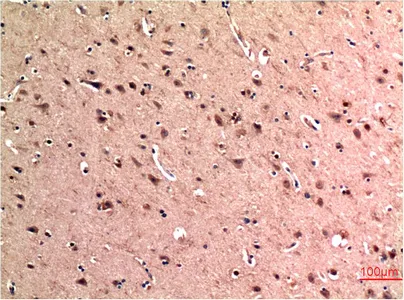

Tau(10E3)Mouse Monoclonal Antibody

HP-1γ(3B9)Mouse Monoclonal Antibody